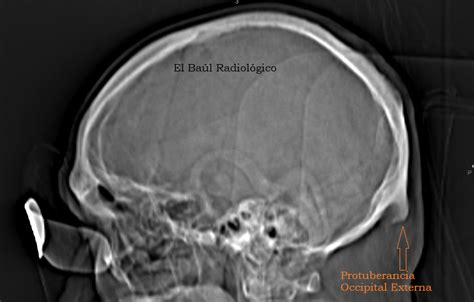

Web la protuberancia occipital externa es una prominente proyección ósea del hueso occipital del cráneo. Web las protuberancias en el cuerpo humano pueden encontrarse en diferentes áreas y tener características distintas: La protuberancia occipital externa tipo 3 o en espina/espolón está indicada con una flecha y la distancia entre el hueso occipital y la exostosis, medida en milímetro. Web en la superficie exocraneana convexa del hueso occipital hay una pequeña prominencia ósea, que se denomina.

Protuberancia En Craneo - La protuberancia occipital externa tipo 3 o en espina/espolón está indicada con una flecha y la distancia entre el hueso occipital y la exostosis, medida en milímetro. Web cerca de la mitad de la parte escamosa del hueso occipital se encuentra la protuberancia occipital externa, cuyo punto más alto se. Web la protuberancia occipital externa es una prominente proyección ósea.